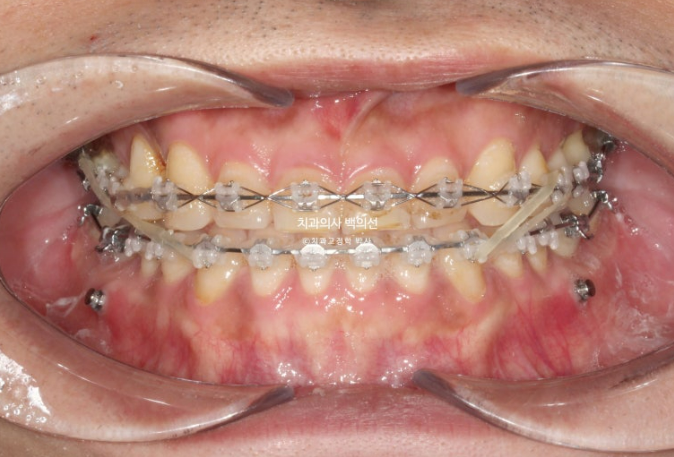

24.02

아래에 미니스크류를 심고 사랑니 공간으로 전체치열을 미는 중 입니다.

가려서 보이지 않던 윗니가 드디어 모습을 드러냈습니다.

교합을 맞추기 위해 고무줄도 끼고 25년 4월, 치료시작 1년 9개월 만에 치료를 종료했습니다